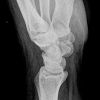

Handgelenk a.p.

Frage nach Bandruptur: gewinkelter Vorderarm liegt flach auf dem Tisch, Handgelenk liegt mit der volarer Seite auf der Kassette, D3 verläuft gestreckt in Richtung Radius.

Frage Fraktur: Finger locker gebeugt, Hand nach lat. abduziert (abgespreizt).

Senkrecht auf Objektmitte und Filmmitte.

Darstellung der Handwurzel- und Unterarmknochen, bei Fragestellung von Epiphysenlösung, Grünholz- oder Os scaphoideumfraktur. Zur Beurteilung der Knochenkerne bei Kindern werden Vergleichsaufnahmen notwendig, bei Verdacht auf Subluxation des Os Lunatums, Zusatzaufnahme in Flextion und Reflextion der Hand notwendig (siehe Stressaufnahme).

Vollständige Abbildung der Metacarpalia, Handwurzelknochen und distaler Unterarm.